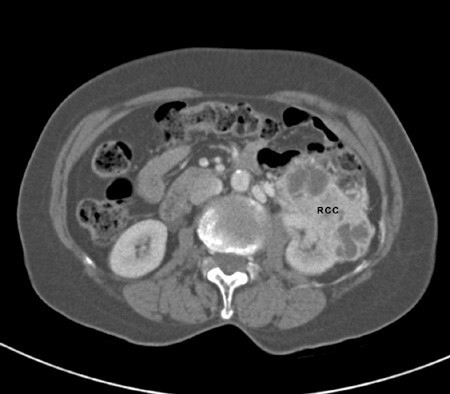

2.Αξονική τομογραφία. Eξέταση εκλογής για επιβεβαίωση της διάγνωσης και σταδιοποίηση πρωτοπαθούς νεφροκυτταρικού καρκινώματος άμεσα μετά την ανεύρεση μάζας νεφρού σε υπερηχογράφημα.

Ρομποτική Νεφρεκτομή

Ο καρκίνος του νεφρού μπορεί να τύχει ίασης, η οποία κατορθώνεται σχεδόν αποκλειστικά από τη ριζική χειρουργική εξαίρεσή του (ο νεφρός και ο όγκος του με όλο το περινεφρικό λίπος). Η ριζική αφαίρεσή του μέσω του ρομποτικού συστήματος DaVinci (ρομποτική νεφρεκτομή), απαιτεί ιδιαίτερη εμπειρία και λεπτότατους χειρισμούς.